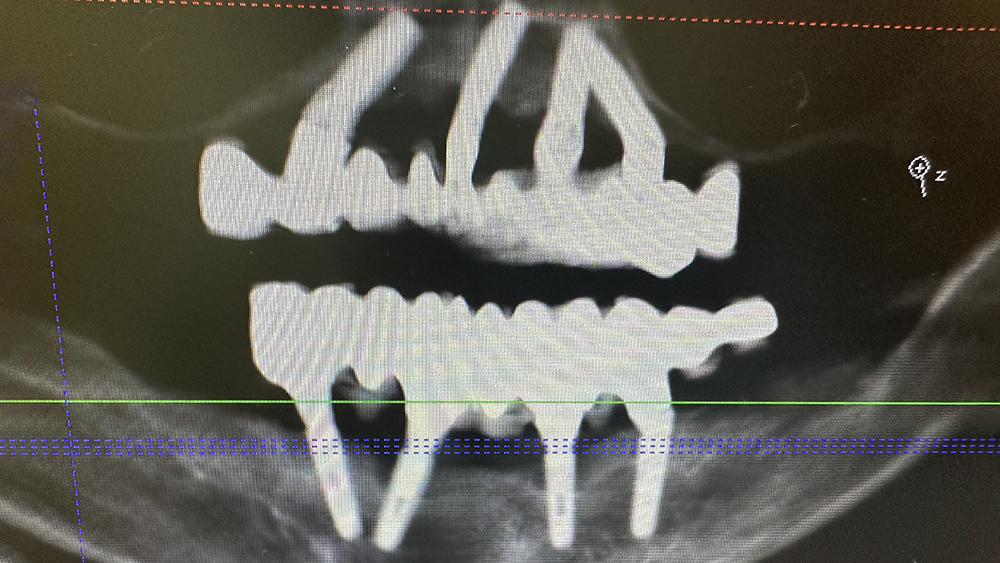

症例4

KYさん、50代男性

治療の期間・回数:約6か月

​治療の価格:約3,300,000円

治療内容:この方は40代で歯がほとんどなく、12年前に上あごに6本、下あごに4本のインプラントを使って、手術当日に仮の歯を入れる「即時荷重」で治療しました。

上の歯は当初、安価な金属のフレームに入れ歯の歯を並べたものを装着しました。

しかし、強い歯ぎしりのため、上の歯は3年で壊れ、修理して再装着しても2年でまた壊れてしまいました。そこで、丈夫なコバルトクロムのフレームにフルジルコニアの歯を接着した最高強度のブリッジに作り替え、見た目を良くするため人工の歯ぐきを付けました。

このブリッジは高価な技工物ですが、約80万円の原価で製作しました。

再装着してから7年経ちますが、今のところ問題なく安定しています。